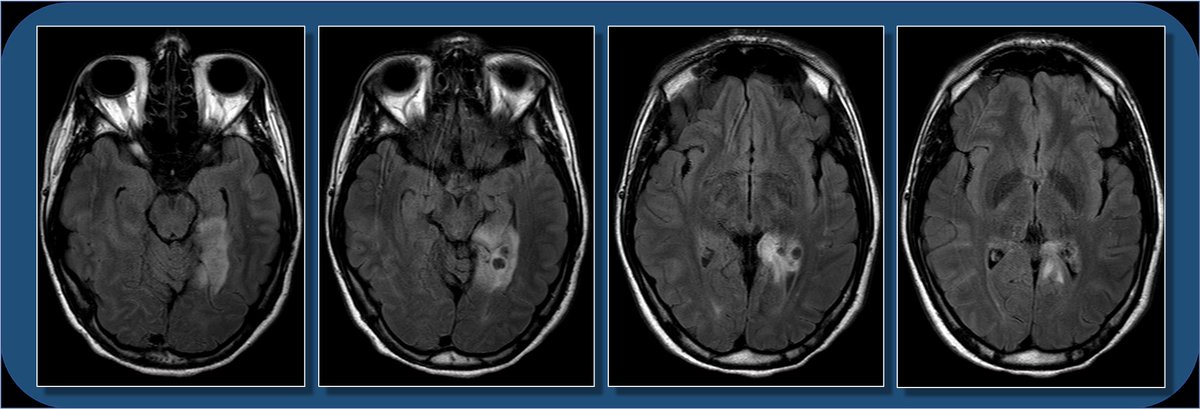

18yoF with seizures. The FLAIR images show focal cortical expansion with cystic components, suggesting a cortically based tumor.

T1 images show mild T1 hypointense mass with cystic components, and minimal if any enhancement. So what’s the differential for a cortically based tumor in a child or young adult who presents with seizure? Pathology following resection c/w ganglioglioma.

Ddx for cortically based tumors in child/young adult includes oligodendroglioma (usually middle-aged adults, often with Ca++), DNET (bubbly, uncommon enhancement), PXA (prominent nodular enhancement), and astrocytoma (usually low grade). Encephalitis can also look similar.

This is less likely to be a glioblastoma, which is usually centered in supratentorial WM, with thick peripheral enhancement, and centrally necrotic.

This location can be a bit difficult to describe if you aren’t up on gyral anatomy. Is it med temporal lobe? occipital lobe? limbic? Describing gyral location is more precise, can explain expected symptoms, and clue in future surgical approach.

The lingual gyrus is involved in holistic visual and word processing, encoding visual memories, imagery, and dreaming. The ganglioglioma in the shown case is centered in the lingual gyrus.

Cingulate g. is part of the limbic circuit; the post cingulate cortex (PCC) is important in default mode network, awareness, pain, and episodic memory retrieval. PCC including the retrosplenial cortex (which together some call restrosplenial gyrus) is involved by the tumor. 11/13